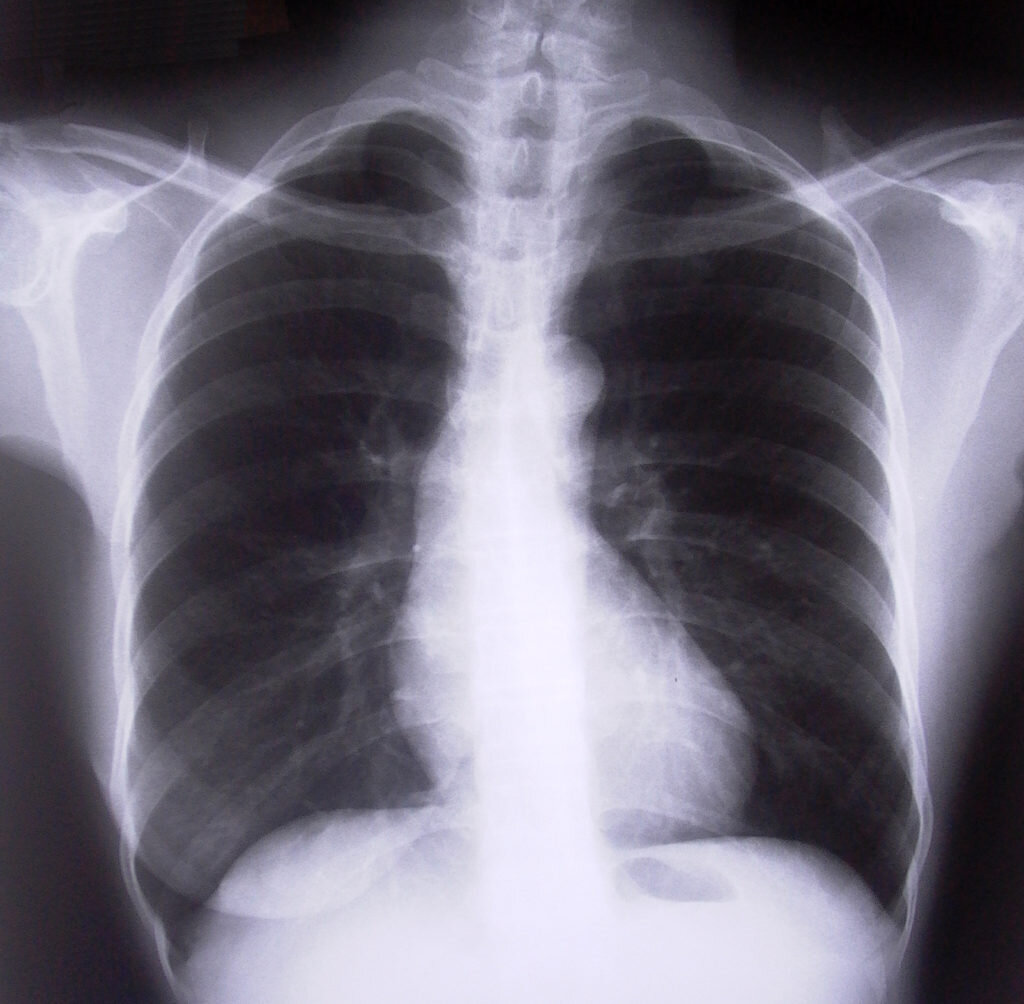

Рак легкого: симптомы известные и не очень

Рак легких — это состояние, при котором здоровые клетки легкого видоизменяются и начинают бесконтрольно делиться, образуя опухоль. Главное правило в лечении любого онкологического заболевания — чем раньше оно обнаружено, тем больше шансов на его полное излечение. При запущенных процессах, когда опухоль глубоко проросла в ткань легкого, поразила лимфоузлы или метастазировала в другие органы, добиться ремиссии сложно, а иногда и вовсе невозможно.

Злокачественные новообразования легких долго никак себя не проявляют, и даже при появлении неприятной симптоматики могут маскироваться под другие болезни. Поэтому важно внимательно относиться ко всем недомоганиям и изменениям в своем организме, особенно если присутствуют неблагоприятные прогностические факторы.